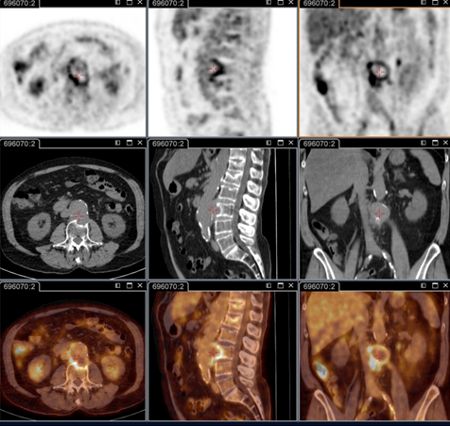

tomografia por emissão de pósitrons (PET)/tomografia computadorizada (TC) com 18-fluordesoxiglucose (FDG)

Exame

Essencial para identificar infecções focalizadas persistentes.[80]

É capaz de decifrar endocardite, infecção vascular, linfadenite e infecção osteoarticular; essas doenças não podem ser identificadas sem essa técnica.

Agora faz parte do check-up anatômico padrão em pacientes com sintomas persistentes e/ou sorologia elevada persistente e/ou reação em cadeia da polimerase positiva no sangue/soro, ou qualquer amostra com quadro clínico não consistente com infecção primária.[3]

É especificamente recomendada em pacientes: com febre Q aguda com IgG de fase 1 ≥1:800 persistente e/ou sinal de evolução desfavorável; com febre Q aguda e história de enxerto vascular ou aneurisma vascular; ou com sorologia inexplicada (IgG na fase 1 ≥1:800) ou suspeita clínica de infecção persistente.

Isso também é útil para identificar infecção em pacientes com prótese vascular e/ou aneurisma, e para identificar candidatos a cirurgia de ressecção dos tecidos vasculares infectados.[Figure caption and citation for the preceding image starts]: Endocardite por febre Q diagnosticada na PET: PET/TC com 18-fluordesoxiglucose. Neste paciente assintomático com história de valva cardíaca e sorologia elevada, a PET permitiu diagnosticar endocardite aórtica na valva nativa com aneurismas micóticos da aorta torácica e lombarInstitut Hospitalo-Universitaire Méditerranée Infection (obtido consentimento do paciente) [Citation ends].

[Figure caption and citation for the preceding image starts]: Aneurisma micótico na aorta torácica da febre Q diagnosticado na PET: PET/TC com 18-fluordesoxiglucose. Neste paciente assintomático com história de valva cardíaca e sorologia elevada, a PET permitiu diagnosticar endocardite aórtica na valva nativa com aneurismas micóticos da aorta torácica e lombarInstitut Hospitalo-Universitaire Méditerranée Infection (obtido consentimento do paciente) [Citation ends].

[Figure caption and citation for the preceding image starts]: Aneurisma micótico na aorta lombar da febre Q diagnosticado na PET: PET/TC com 18-fluordesoxiglucose. Neste paciente assintomático com história de valva cardíaca e sorologia elevada, a PET permitiu diagnosticar endocardite aórtica na valva nativa com aneurismas micóticos da aorta torácica e lombarInstitut Hospitalo-Universitaire Méditerranée Infection (obtido consentimento do paciente) [Citation ends].

Resultado

positivo na infecção focalizada persistente (por exemplo, valva cardíaca, foco vascular da linfadenite, linfonodos, foco osteoarticular)